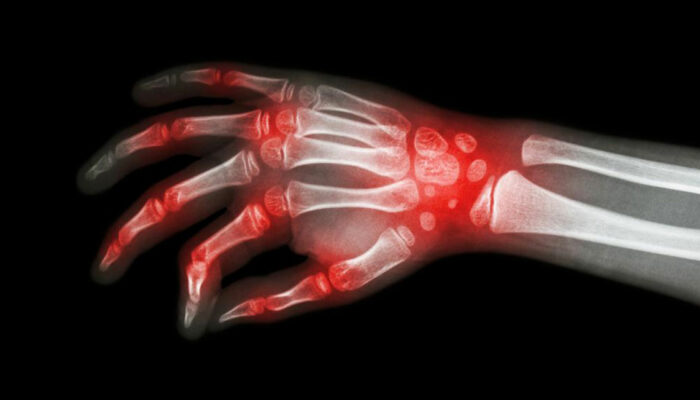

The most shared and evident similarity that rheumatoid arthritis and lupus share is joint pain. However, the levels of inflammation and swelling of joints may vary between these conditions. Joint pain is also a common symptom of patients diagnosed with either rheumatoid arthritis and lupus. Also, the joints can become warmer and tender, though this is a more prominent symptom of rheumatoid arthritis.

It is these similarities that cause a lot of confusion with the diagnosis of rheumatoid arthritis and lupus. There are several times when patients are diagnosed with rheumatoid arthritis when they actually have lupus. This usually happens in the early stages of the disorder. As the condition progresses, the difference becomes evident; rheumatoid arthritis causes bone deformity and erosion while lupus rarely leads to bone erosion.